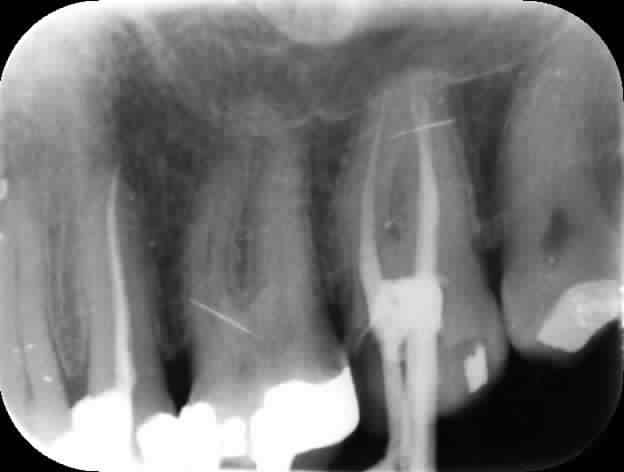

Voici toutes les radios du début à la fin :

On touche au but après 2H 30 de dépose-retraitement. Mv2 en Y heureusement pour moi. Obturation gutta chaude le tout pour 2 balles.

Le mystère reste entier concernant le canal palatin, la gutta ayant disparue probablement lors de la réalisation du tenon.

Le réchauffement de la pèche palatine a eu lieu 8 ans après.

haa , je suis allée trop vite, je me disais: c'est quoi cette radio argentique au milieu des numériques ..t'es donc allé récupérer la radio chez celui qui t'avait fait le travail .... le cone est donc parti au moment du logement de tenon ... il a du faire cela dans la même séance que l'endo .. trop pressé .....

Et la radio où on ne voit pas l'apex ? ?? Bon sang, quel travail de sagoin !!!

C'est du digora, envoyé par mail. Et non le logement n'a pas été fait lors de la séance de l'endo. Pour les autres si il manque un apex, mea culpa c'est pas évident de s'auto radiographier surtout pour une 7.